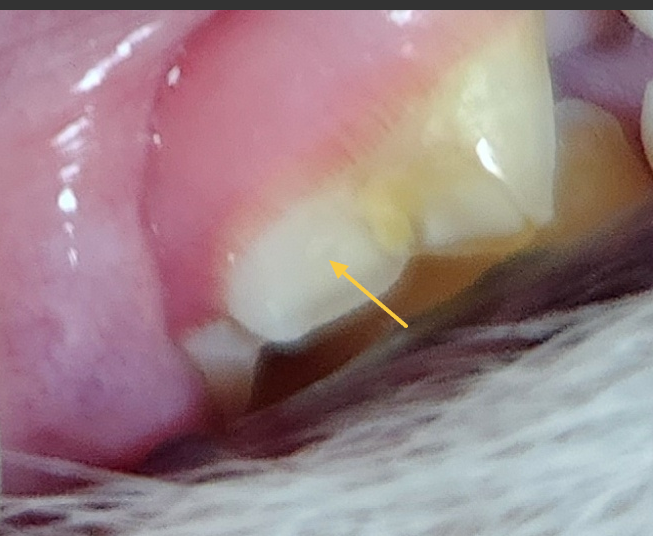

강아지 어금니 파절인데 발치해야할까요?ㅠ

파절후 2주안에 치료해야한다는데

5일 저녁에 파절된거같은데 통증은없고

일이 쉬는날이 없어서 빨라도 9일 혹은 16일에 해줄수있는데 괜찮을까요?ㅠㅠ

화살표에 이미 치수강이 노출되어 신경관에 감염이 유발된 상태로서 신경치료를 받아 치아를 수복하거나 발치가 지시되는 상태로 보입니다. 주치의와 상의하시기 바랍니다.